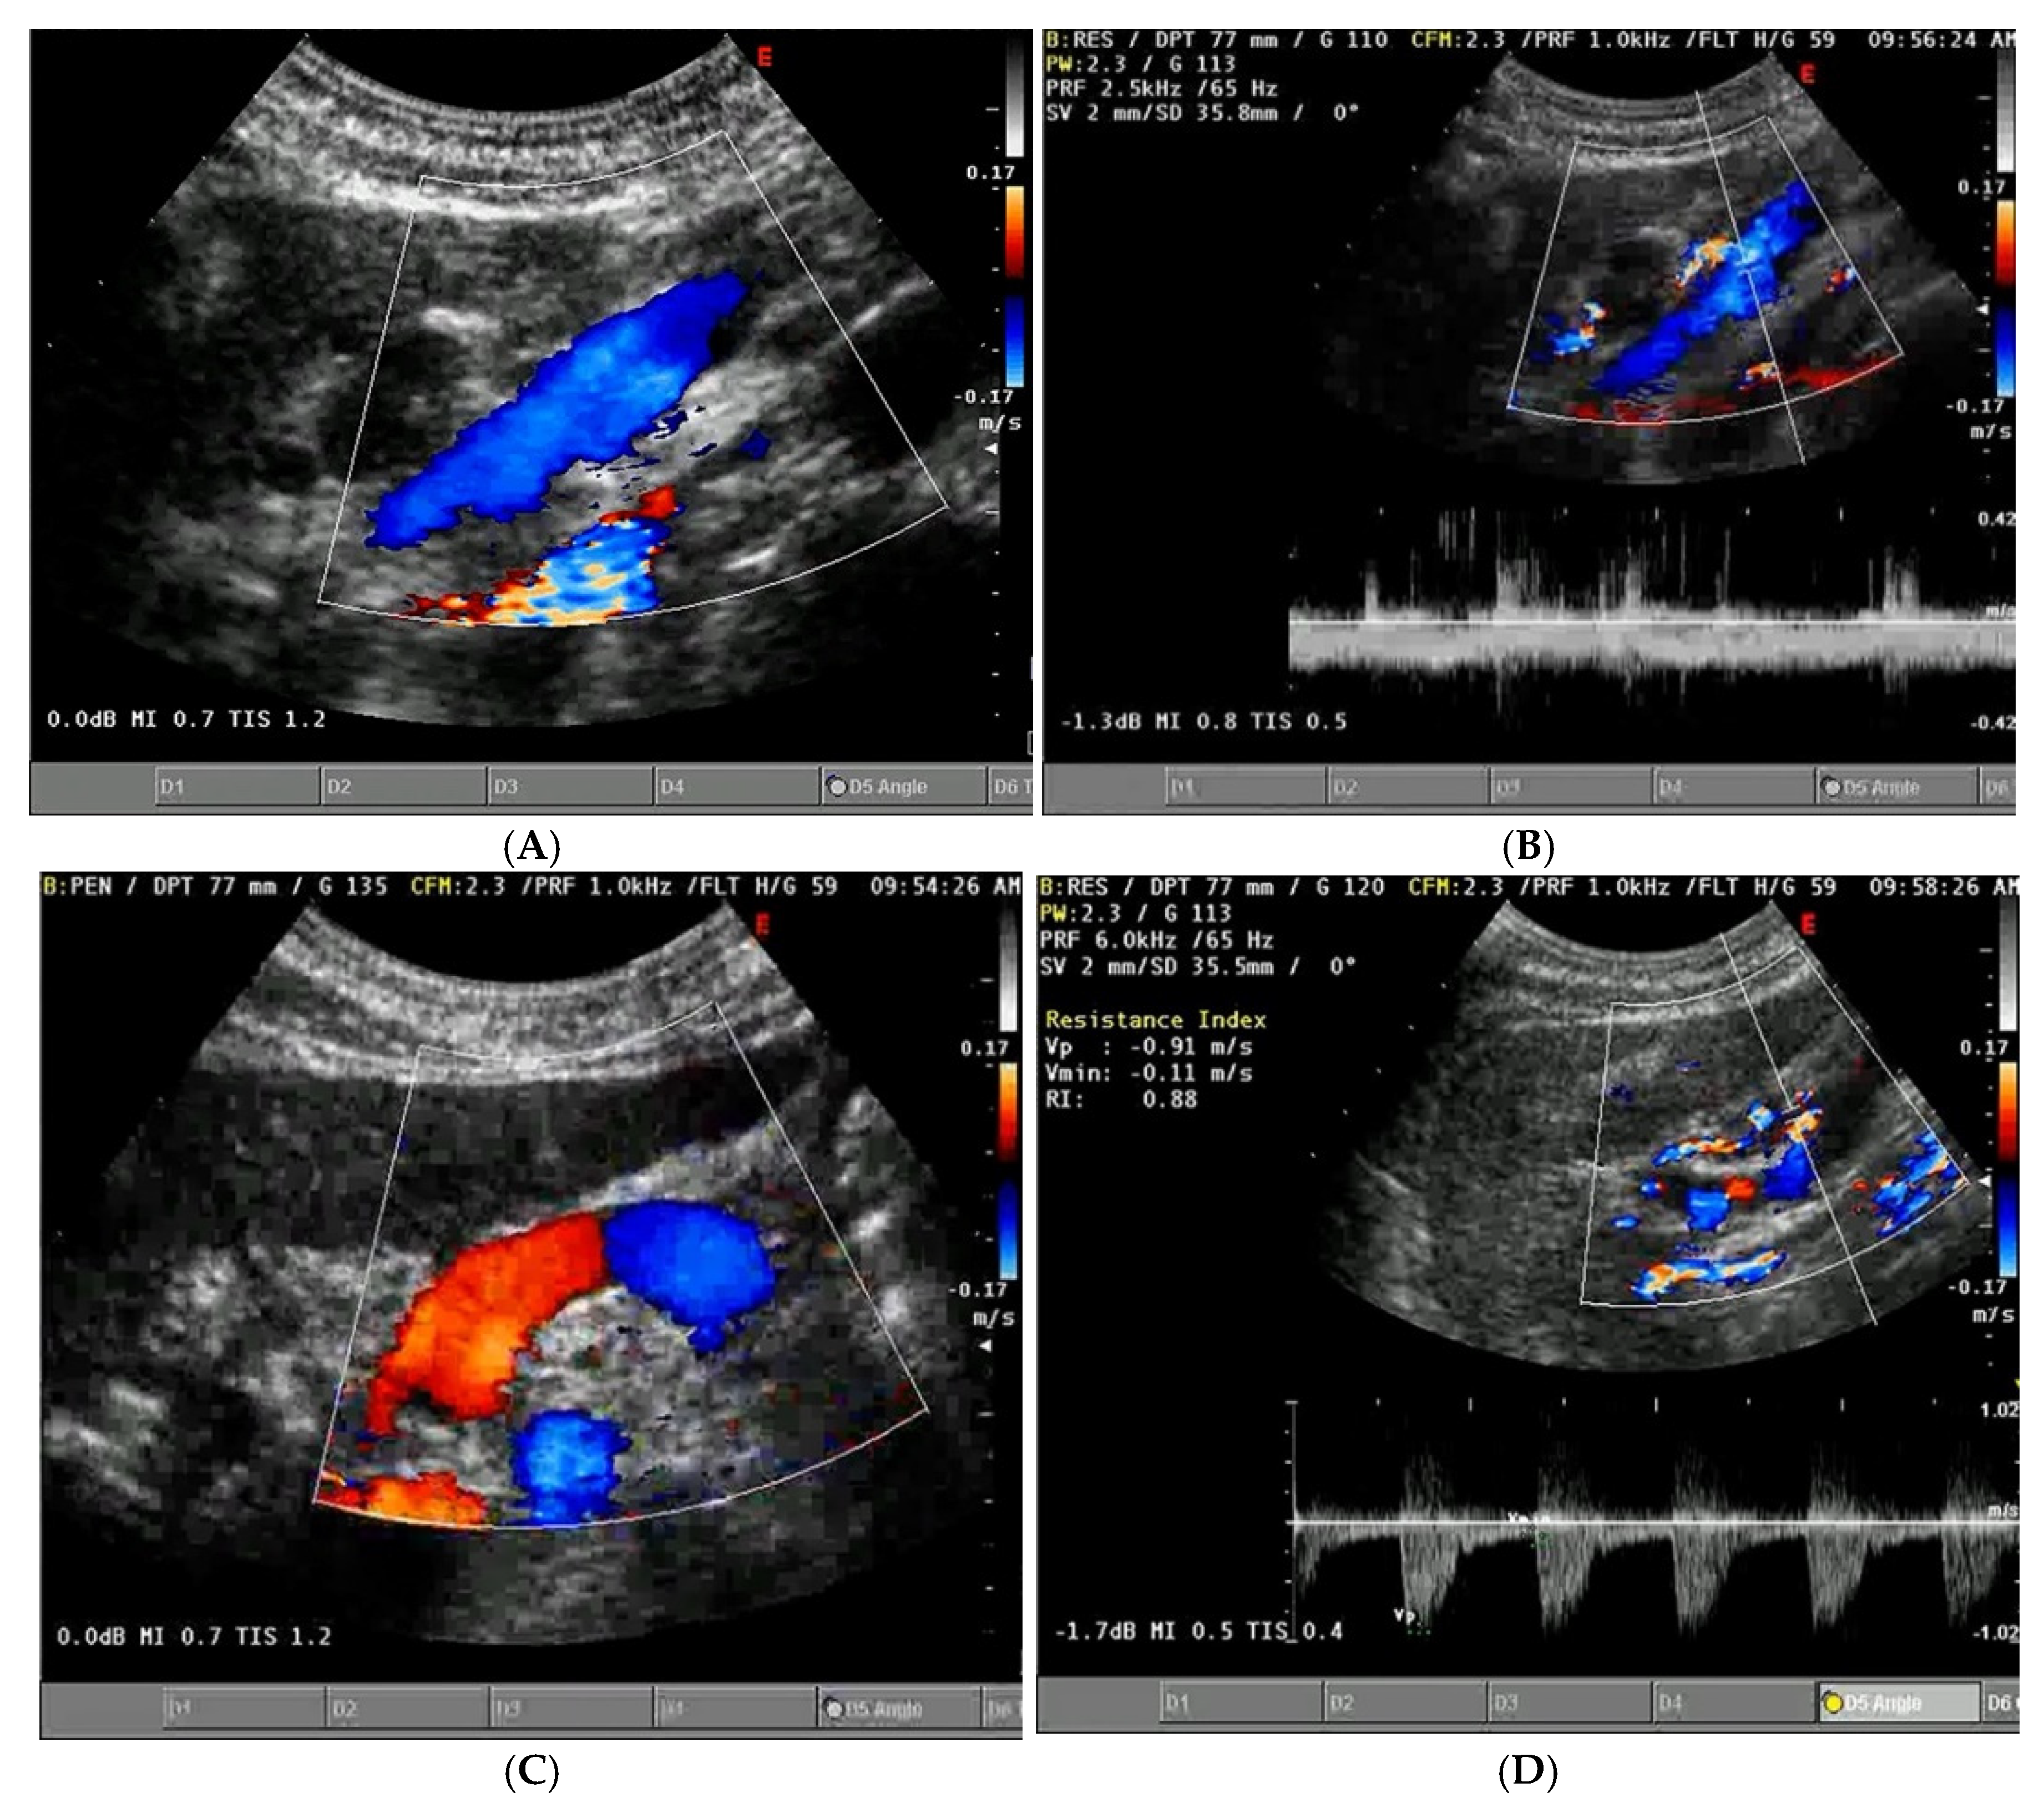

- Increased Pulsatility (Pulsatile Waveform): A pulsatile portal venous flow occurs when there is a significant difference between peak systolic and end-diastolic velocities. This is due to abnormal transmission of pressure through the hepatic sinusoids, often caused by conditions like tricuspid regurgitation, right-sided heart failure (CHF), or arteriovenous shunting (as seen in cirrhosis or hereditary haemorrhagic telangiectasia (Figure 9A) [105]. Pulsatility can be differentiated clinically, with right-sided CHF and tricuspid regurgitation identifiable through the hepatic venous waveform and grayscale US showing dilated hepatic veins, unlike in cirrhosis, where hepatic veins are compressed.

- Slow Portal Venous Flow: Slow flow occurs when back pressure restricts forward flow, typically indicating portal hypertension. In these cases, peak velocity is less than 16 cm/s [106]. Causes of portal hypertension include cirrhosis, portal vein thrombosis (prehepatic), and right-sided heart failure (posthepatic). The most specific findings include the development of portosystemic shunts (like a recanalized umbilical vein) and slow or reversed (hepatofugal) flow.

- Hepatofugal (Retrograde) Flow: Hepatofugal flow happens when the pressure in the portal vein exceeds that of the liver, causing flow to reverse and appear below the baseline. This is another indicator of portal hypertension, which can be caused by various conditions, including cirrhosis, right-sided heart failure and other portal vein obstructions [107] (Figure 9).Figure 9. (A) Increased pulsatility due to arteriovenous shunting in a case of hereditary haemorrhagic telangiectasia; (B) Reduced Portal Flow in a case of cirrhosis (C) Hepatofugal Flow of Portal Vein is a late sign of Portal Hypertension. It happens when the pressure in the portal vein exceeds that of the liver, causing flow to reverse and appear below the baseline. This is another indicator of portal hypertension, which can be caused by various conditions, including cirrhosis, right-sided heart failure and other portal vein obstructions.Figure 9. (A) Increased pulsatility due to arteriovenous shunting in a case of hereditary haemorrhagic telangiectasia; (B) Reduced Portal Flow in a case of cirrhosis (C) Hepatofugal Flow of Portal Vein is a late sign of Portal Hypertension. It happens when the pressure in the portal vein exceeds that of the liver, causing flow to reverse and appear below the baseline. This is another indicator of portal hypertension, which can be caused by various conditions, including cirrhosis, right-sided heart failure and other portal vein obstructions.